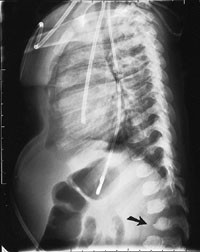

Pasienten ble så 13 måneder gammel innlagt i barneavdeling i forbindelse med ny feberepisode. Ved innleggelsen var han dystrofisk, med stor abdomen, tynne ekstremiteter og slunkne nates. Noe grove ansiktstrekk ble bemerket, men gav ikke umiddelbart videre assosiasjoner. Utredning av malabsorpsjon med tanke på cøliaki ble startet. Metabolsk screening av urin og serum ble rekvirert. Røntgen thorax viste klare lunger og et normalt stort hjerte, men påfallende brede costae (fig 1). Fysioterapeutisk vurdering bemerket en forsinket motorisk utvikling og stive ledd. Øre-nese-hals-undersøkelse viste betydelig nasalstenose og hypertrofiske tonsiller. Foreldrene kunne fortelle om uttalt pustebesvær og sterk snorking om natten, med tendens til pustestopp. Primær malabsorpsjon og cøliaki ble utelukket med serologiske prøver. Ultralyd abdomen viste leverstørrelse i øvre normalområde.

Omfattende radiologisk utredning ble rekvirert. Røntgen av kraniet viste et relativt stort nevrokranium (fig 2) med sannsynlig fortykket calvarium i basale deler. Røntgen av columna viste en kyfotisk knekk på torakolumbalovergangen (fig 3). Røntgen av bekken viste dysplastiske hofter bilateralt (fig 4). Røntgen av håndledd viste forandring av metakarpene. Røntgenologenes endelige konklusjon var dysostosis multiplex, forenlig med Hurlers syndrom. Undersøkelse hos øyelege styrket denne mistanken ytterligere, da det ble funnet bilateral, diffus tilsløring av hornhinnene. Plastisk kirurg bekreftet at det forelå triggerfinger på høyre hånds 4. finger, et typisk funn ved Hurlers syndrom.